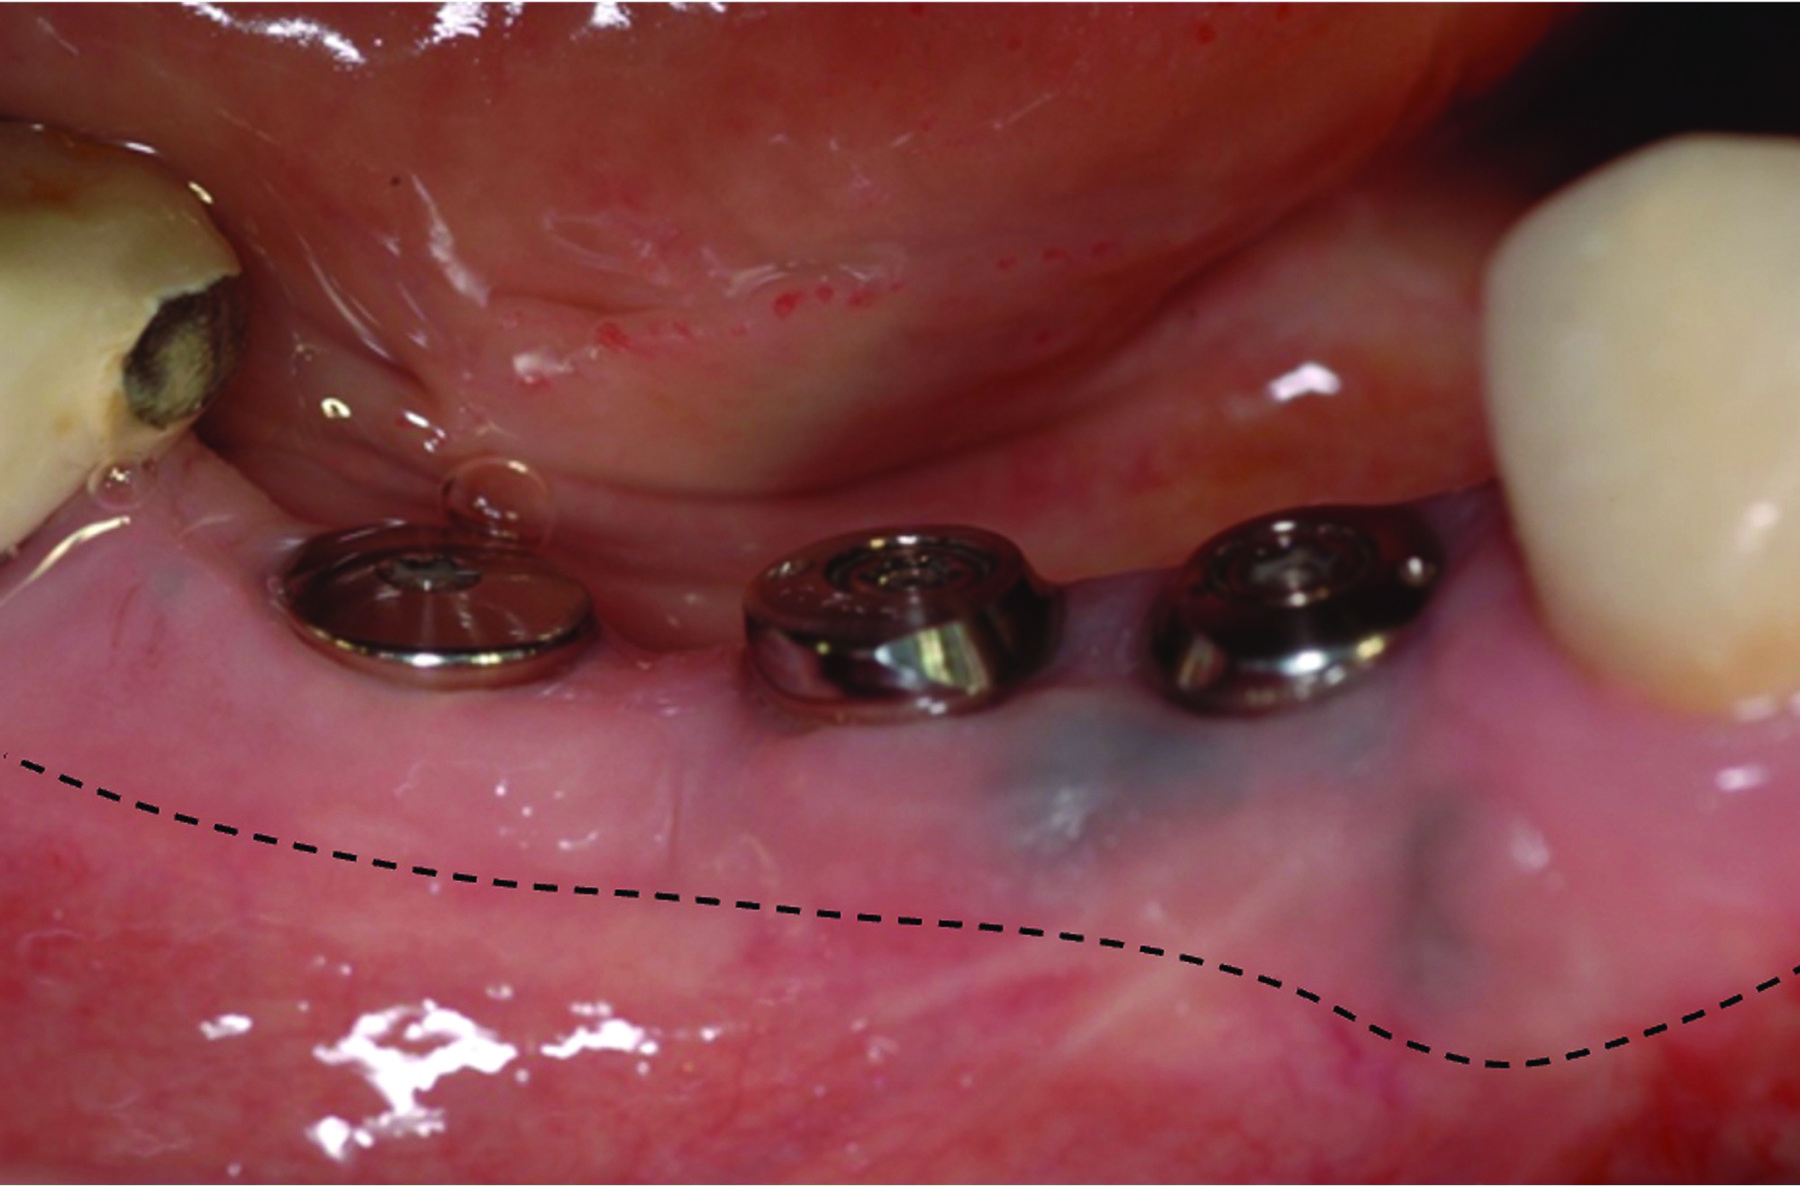

Fig 6 through Fig 8. Example of increasing KMW with an APF at implant uncovery. Fig 6: initial presentation showing lack of KMW; Fig 7: healing abutment placement with APF; Fig 8: 2 months post-treatment. (The dotted lines indicate the MGJ.) Fig 9 through Fig 11. Example of increasing KMW with an APF and FGG at implant uncovery.